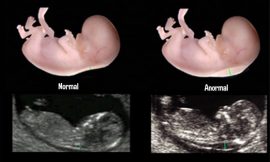

Por meio desse exame é possível detectar se existe algum tipo de problema ou anomalias no feto. Como vários desses problemas podem ser solucionados quando são descobertos precocemente, é essencial que o exame seja feito durante o pré-natal, de modo a evitar possíveis complicações que podem colocar em risco tanto a vida do bebê quanto a da mãe.

- Observar se existe algum tipo de anomalia congênita no feto;

Nessa etapa da gravidez também já se pode verificar se há o risco de síndrome de Down ou outros tipos de anomalias por meio do ultrassom.

Já o ultrassom obstétrico com translucência nucal, além de informar a duração da gravidez, faz a medição de um espaço que existe na nuca do feto, avaliando o acúmulo de líquido. Isso ajuda a identificar se existe ou não alguma anomalia, como a síndrome de Down (que, no caso, deve ser confirmada com a combinação de outros exames).

O ultrassom morfológico também não requer preparação. No primeiro trimestre ele indica se existe o risco de alterações estruturais e doenças genéticas no bebê. Já no segundo semestre, é avaliada detalhadamente a morfologia do feto, onde é possível excluir por volta de 85% de possíveis más formações.